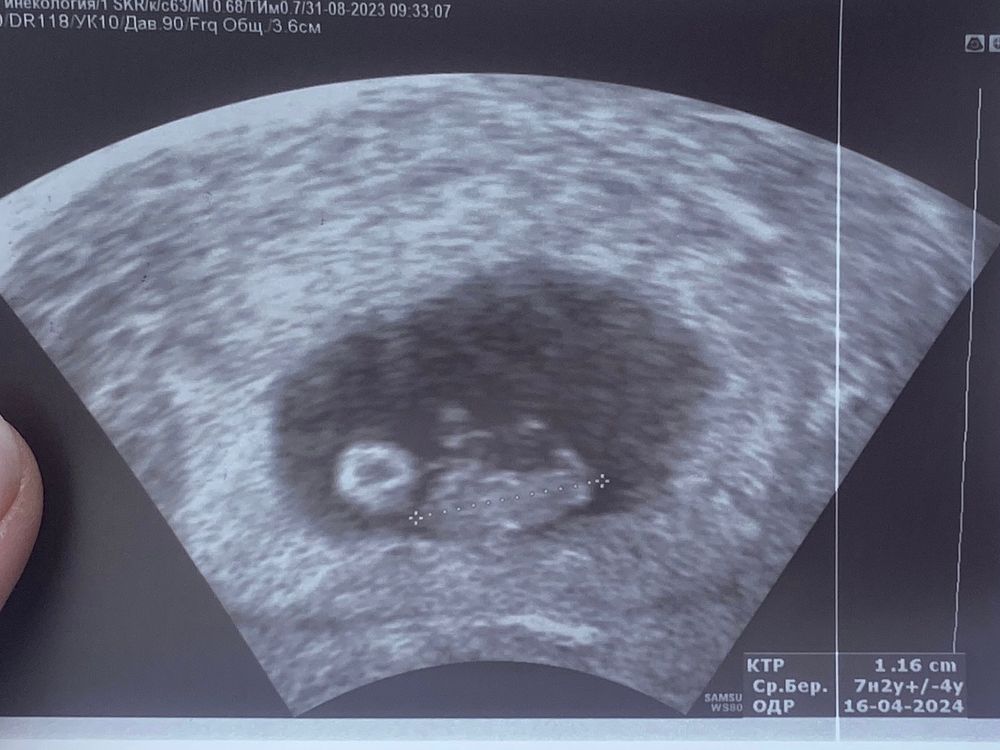

7+2 по УЗИ

Сегодня должно было быть 7 недель ровно по овуляции (+2). По итогу на узи 7 недель и 2 дня)

Видно нашу булочку, сердцебиение 138, ктр 11,6 мм ☺️

Изображение